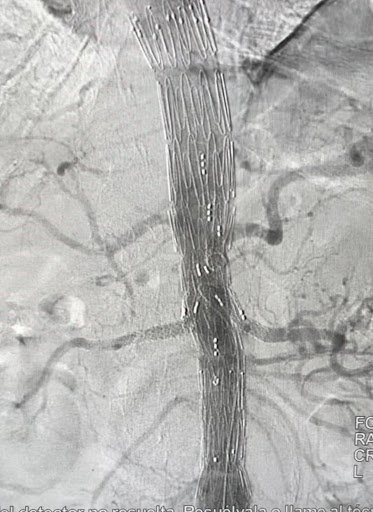

Antes: Oclusión bilateral ilíaca

Antes

Oclusión de ambas venas ilíacas/Sindrome de congestión pélvica

Después: Reconstrucción con stents

Después

Reconstrucción con stents. Flujo normalizado y resolución clínica.